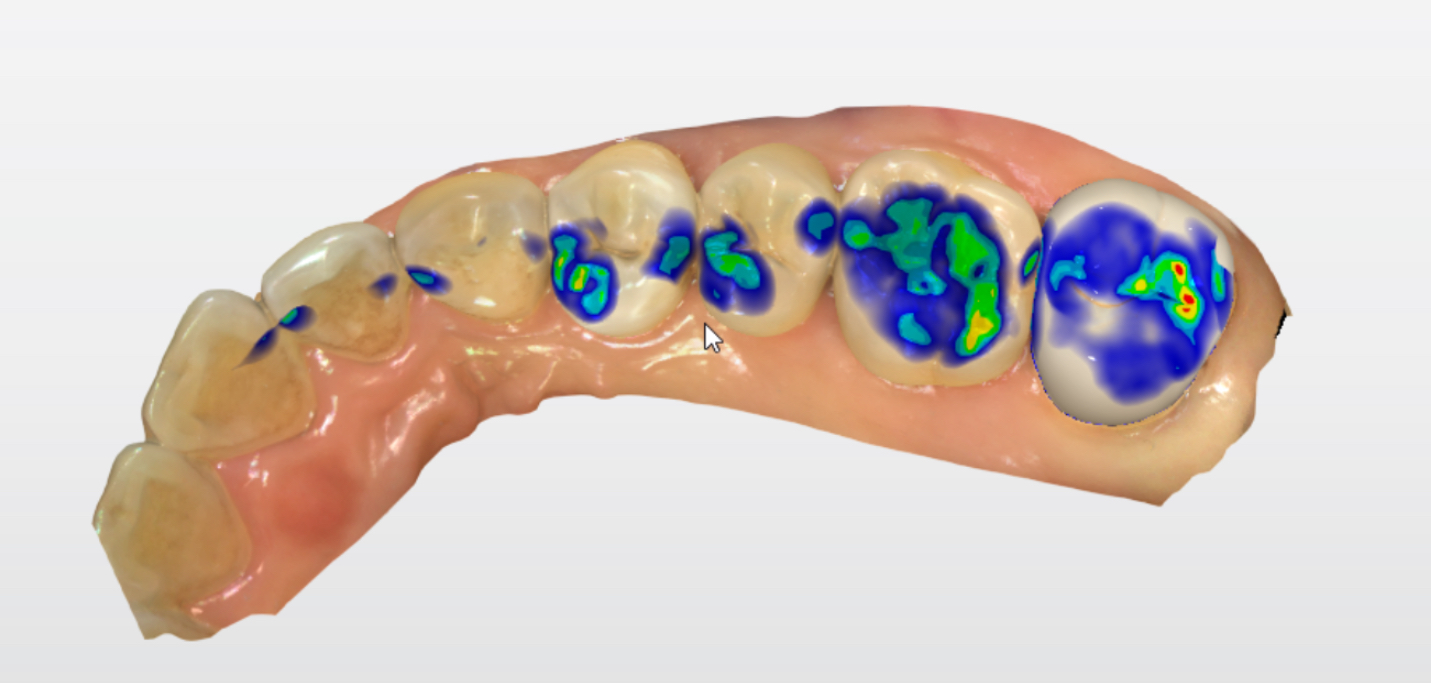

该患者就是因为咬硬物导致牙齿近远中横向隐裂,波及到牙髓时,牙齿受到细菌感染出现自发的疼痛症状,此时必须及早进行根管治疗来缓解疼痛。在进行彻底的根管治疗后,还需要进行冠修复来保护牙齿不再进一步裂开。

根管治疗后的牙冠修复是避免牙齿折断、延长使用寿命的关键步骤。根据牙齿位置和需求选择合适材料,并严格维护,可确保修复效果长期稳定。越早保护,越省成本!

所以,为了避免这种风险的出现,医生通常会在根管治疗修复后,为患者做一个新的牙冠或者高嵌体将牙齿保护起来。